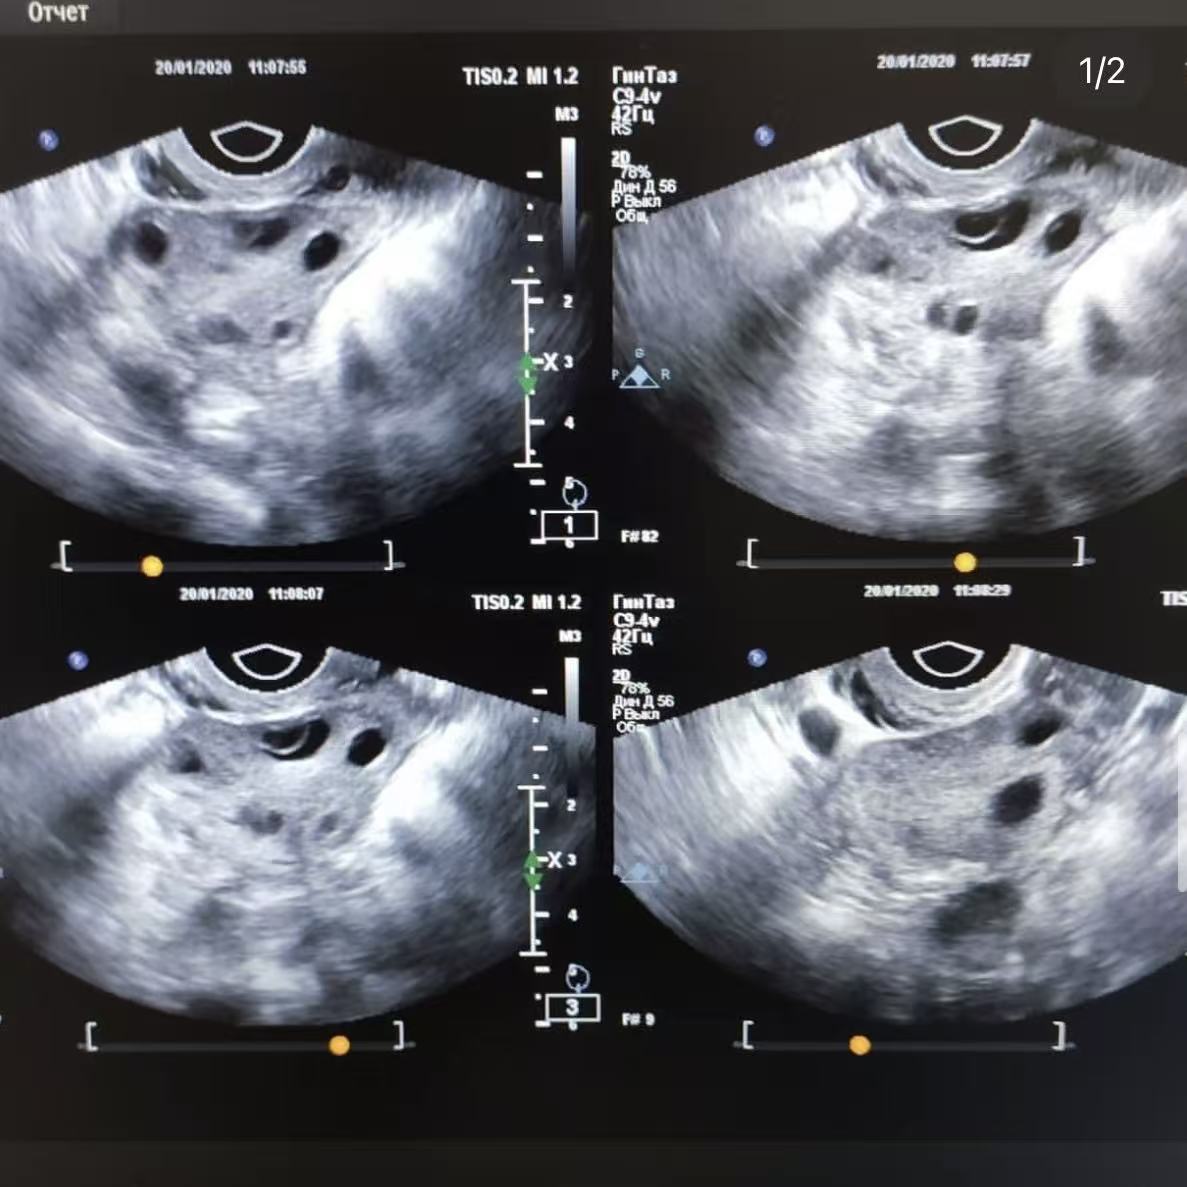

阴超

用于评估卵巢基础卵泡数量及生殖系统结构状态